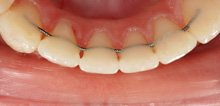

Indirekte Klebetechnik

Das indirekte Klebeverfahren wurde zur Verbesserung der Positionierungsgenauigkeit der Brackets und zur Verringerung der Unannehmlichkeiten für den Patienten eingeführt. Hierbei werden die Brackets reversibel auf die Situationsmodelle geklebt und in einem aufwändigen Verfahren individuelle Übertragungsschienen angefertigt. Dadurch erfolgt der Einbau der „festen Spange“ nicht nur mit maximaler Genauigkeit, sondern auch komfortabler und in wesentlich kürzerer Zeit für die Patienten.

Der wesentliche Vorteil dieser Methode liegt jedoch in einer deutlich kürzeren Behandlungszeit für die Patienten, da die festsitzende Spange auf Grund der höheren Genauigkeit der Bracketpositionen wesentlich früher wieder abgenommen werden kann.